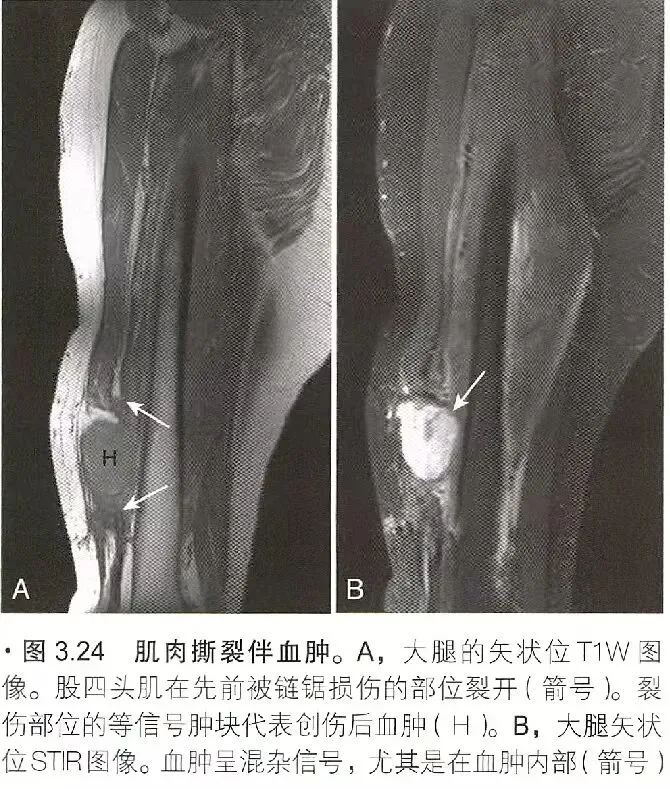

肌肉创伤

肌肉创伤可分为间接肌肉损伤、直接肌肉损伤和其它肌肉损伤。